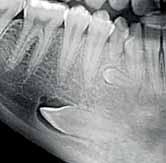

The Dental Panoramic Tomogram (DPT) confirmed the presence of all permanent teeth including the developing third molars (Figure 3). Root morphology appeared normal. The upper right central incisor had a root canal filling. The upper standard occlusal

radiograph revealed that the upper right central incisor had an adequate root filling with no periapical area. In the cephalometric assessment (Figure 4), the ANB value of 7° suggested a moderate Class II skeletal pattern. The vertical proportions were within normal values. The upper incisors were proclined at 122° and the lower incisors were of average inclination at 94°. The interincisal angle was reduced at 119°. The lower incisor to APo and the lower lip to E line were within normal limits.